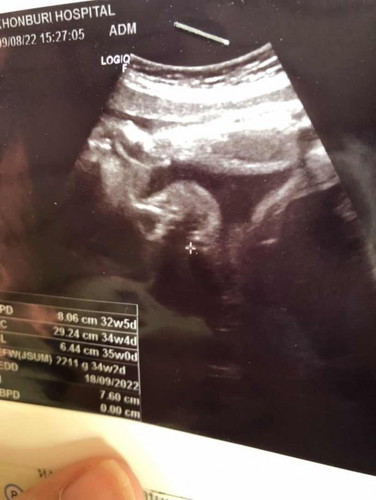

ในภาพคือส่วนไหนของน้องค่ะ เราดูภาพไม่ค่อยเป็น

มองไม่ออกเลยค่ะว่าส่วนไหน น้องตัวใหญ่แล้วจะดูยากหน่อยค่ะแม่